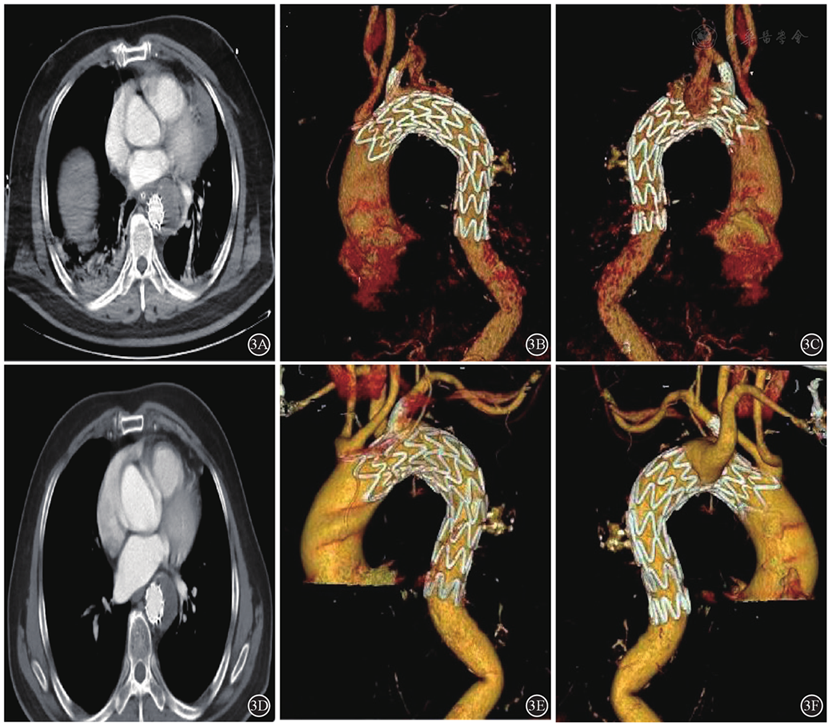

图3 患者出院后随访影像结果3A~3C:术后1个月,心包积液、胸腔积液明显吸收,使用双开窗技术重建LSA、保留ARSA,CTA三维重建图像显示假腔被封闭,弓部分支动脉均保持通畅,Kommerell憩室未扩大;3D~3F:术后3个月,心包积液、胸腔积液完全吸收,CTA三维重建图像显示LSA、ARSA均保持通畅,Kommerell憩室无变化。